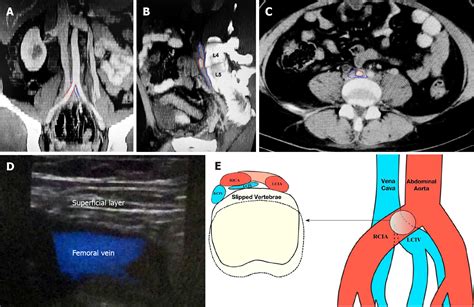

Understanding May Thurner Syndrome (MTS), also known as iliac vein compression syndrome, is crucial for those experiencing persistent, unexplained leg pain or swelling. This condition occurs when the right iliac artery compresses the left iliac vein against the lumbar spine. This structural anatomical anomaly restricts blood flow from the lower body back to the heart, significantly increasing the risk of developing deep vein thrombosis (DVT). While often asymptomatic in its early stages, failing to recognize the signs can lead to severe health complications. Recognizing the underlying anatomy and the mechanisms behind this syndrome is the first step toward effective management and long-term vein health.

At its core, May Thurner Syndrome is a vascular condition where the right common iliac artery presses down on the left common iliac vein. This constant pressure causes irritation to the vein wall, which can lead to the formation of scar tissue inside the vein, known as a "spur." This obstruction makes it difficult for blood to drain properly from the left leg and pelvis.

Diagnosing May Thurner Syndrome requires specialized imaging because the symptoms can mimic other vascular issues like chronic venous insufficiency or simple DVT. Physicians typically use a combination of the following tests:

• Duplex Ultrasound: Often the first line of defense to visualize blood flow and identify potential clots.

• CT Venogram or MR Venogram: Provides highly detailed cross-sectional images of the pelvic veins to confirm the level of compression.